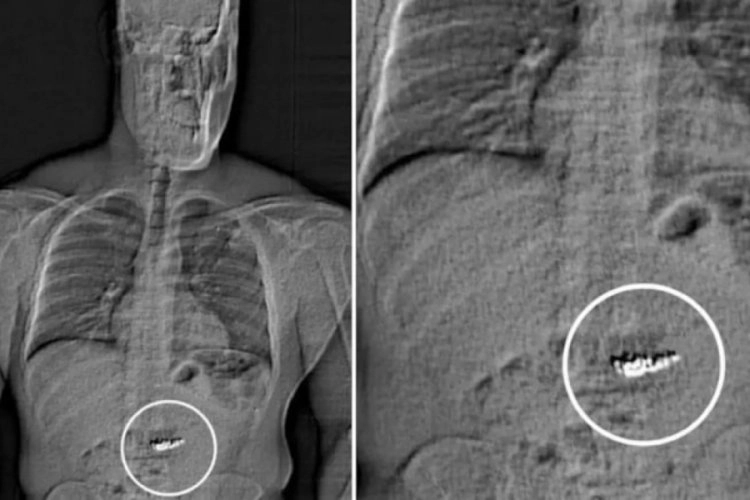

Hapishanede bulunan Gilder, bir anda yetkililere "Midemde olanlar için suçlanacak mıyım?" diyerek kendisini ele verdi. Gilder'e yapılan vücut taramasında sindirim sisteminde yabancı cisimler (küpeler) tespit edildi.

Raporda, "Bu yabancı cisimlerin, soygunda çalınan Tiffany&Co küpeleri olduğu düşünülüyor ancak Gilder'in sisteminden çıktıktan sonra toplanarak doğrulanması gerekecek" ifadeleri yer aldı.